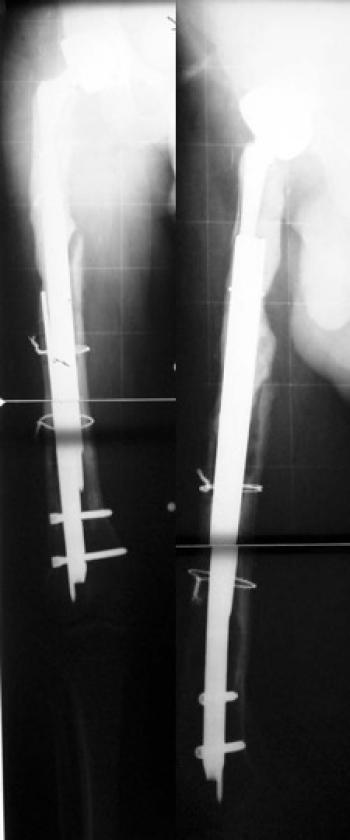

17 yaşında erkek hastada ateşli silah yaralanması sonucu sağ femurda oluşan 14 cm kemik defekti ve 5 cm kısalığın, önce eksternal fiksatör i...